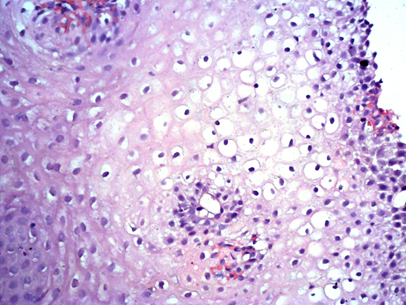

A PAS reaction showed a heterogeneous focal decrease in color in areas of inflammation, proliferation and degeneration of the epithelium, which reflected a decrease in mucus secretion, a sharp decrease in mucus secretion in the submucosal layer (Figure 2).

Figure 2 A fragment of esophageal mucosa, an area of papillomatosis, a sharp decrease in mucus formation. PAS reaction, 50x magnification.